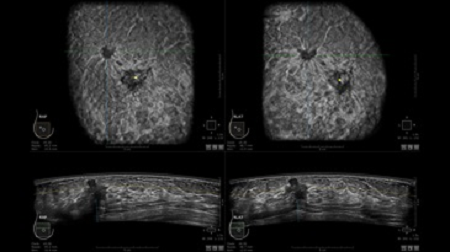

GE INVENIA ABUS – это современный УЗИ аппарат, который создан для точной и эффективной диагностики сканирования с высокой плотностью молочных желез. Выявляемость патологий раковых и предраковых стадий заболевания составляет 55%, что в конечном счете позволяет ставить врачу точные и своевременные диагнозы. Традиционные методы использования маммографии не показывают такой выявляемости, ограничиваясь лишь 3-38%.

УЗИ-аппарат GE INVENIA ABUS позволяет проводить максимально операторонезависимые процедуры, что значительно снижает риск неправильной постановки диагноза и сопутствующие издержки на обработку информации. Система готовит отчет в течение 3-х минут после сканирования, это безусловное преимущество по сравнению с обычным УЗИ сканером.

• Отображение объемных 3D ультразвуковых изображений, которые состоят из традиционных поперечных и воссозданных коронарных и сагиттальных проекций

• Стандартизованная ориентация изображения: «толстый срез» в коронарной плоскости; поперечная; сагиттальная плоскость; радиальный и антирадиальный поворот изображения; просмотр исключительно области интереса

• Одновременный просмотр двух изображений для сопоставления в коронарной плоскости